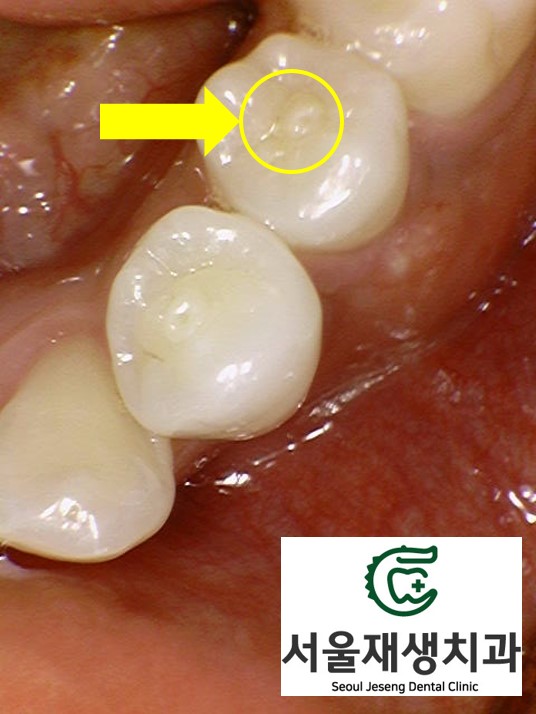

![[치외치신경치료] 뿌리 끝 염증이 커서 발치해야된대요! 치아 머리에 볼~록! 알고보면 무서운 작은 혹 (서울재생치과) 관련 이미지 23](https://pub-9f2bb3498faf4d1d8714b41df24753e3.r2.dev/content/clinics/archive/nqmm0udu86/naver_blog/honeybeevuvu/assets/by_hash/4369335606deb491853f4df7082f991c89141c675f9c8c4d0a322a987fd9bb9d.jpg)

이 치아의 경우

큰 파절이나 충치가 없었기 때문에,

신경치료를 할 때 형성했던 작은 구멍을

레진으로 매꿔주는 것으로 충분합니다.

(본래 치아 상태에 따라 크라운이 필요한

경우도 있습니다^^)

3개월 남짓한 긴 치료 기간동안

꾸준히 내원하시어

치료에 협조해주신 환자분께

감사드립니다.